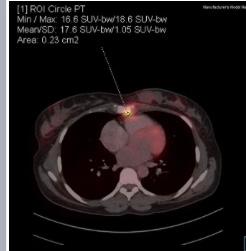

Mammogram Left MLO view shows a circumscribed high-density round to oval lesion in the upper quadrant near the axillary tail. Another partially visible high-density lesion is seen in the lower inner quadrant posterior third of the breast ( retroglandular zone) near the chest wall. Corroborative USG of the upper outer quadrant lesion revealed a hypoechoic round to oval lesion with microlobulated margins while the lower inner quadrant lesion revealed an anechoic collection with fine internal echoes reaching up to the chest wall with areas of bone erosion of the sternum. CT was done to see the extent of collection and other lesions which showed a hypodense collection in the chest wall near the sternum with areas of bone erosion and a hypodense round to oval lesion near the axillary tail. PET CT was done for academic purposes which showed uptake from the chest wall lesion near the sternum with no uptake in the hypodense collection. Biopsy was done from both the upper outer quadrant and chest wall lesion.